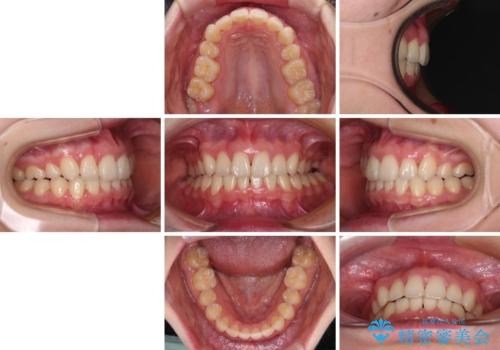

上顎のみの抜歯矯正 前歯のデコボコを改善する

奥歯の咬み合わせがなかなか定まらず、スペースが閉じるまでに時間がかかりましたが、最終的には正中を合わせることもできました。